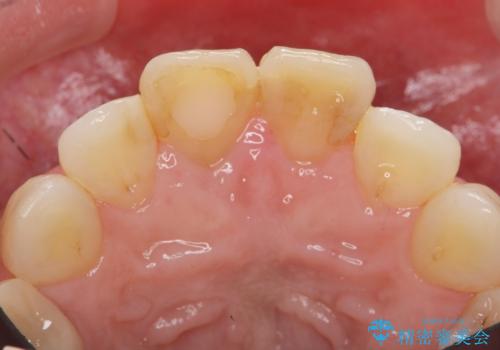

リアルな歯の色調にこだわるオールセラミッククラウン治療

- 歯の神経を除去したのちの、変色の改善を希望され来院されました。

再度根管治療を行ったのちの、オールセラミッククラン治療を計画します。

天然歯を再現したリアルな仕上がりに満足いただくことができました。

オールセラミッククラウン スペシャルプランは細やかな色調の再現に優れ、目立つ前歯の審美的な仕上がりがより達成されやすいプランです。